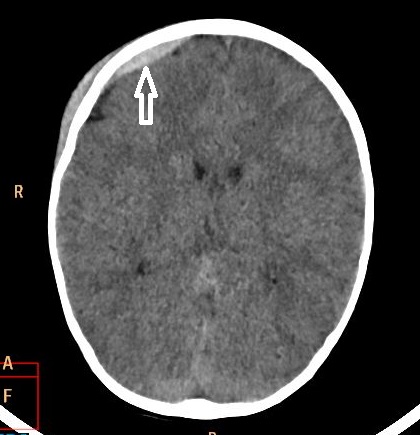

Przypadek 11: 2-letnia dziewczynka, siedziała zapięta w foteliku na rowerze. Rower upadł razem z pacjentką, dziewczynka nie miała kasku. Nie straciła przytomności. Po urazie kilkakrotnie wymiotowała. Badanie TK głowy.

Rozpoznanie: W tomografii komputerowej uwidoczniono krwiak nadtwardówkowy o wym. ok. 40x6mm w prawej okolicy czołowej. Poza tym mózgowie bez widocznych zmian ogniskowych w badaniu jednofazowym, bez cech uogólnionego obrzęku. Struktury pośrodkowe nieprzemieszczone.Kości czaszki bez zmian pourazowych.